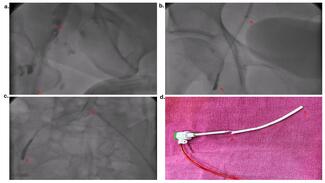

Marco A. Alcántara-Meléndez, MD; Antonio Vargas-Cruz, MD; César L. González-Aguilar, MD; Faustino J. Silva-Centeno, MD; Jesus González-Jasso, MD; Leonel Avendaño-Perez, MD; Rafael Esparza-Corona, MD; Heberto Aquino-Bruno, MD

The authors show an example of microcatheter over-torquing, causing entrapment of the guidewire during recanalization of a chronic total occlusion,.